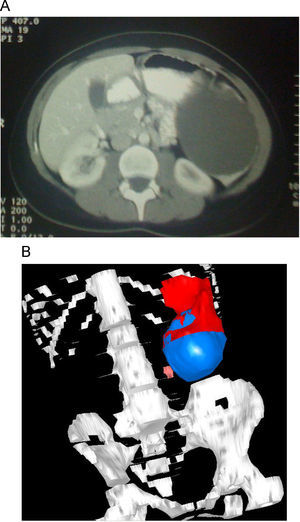

Caso clínicoPaciente de 26 años diagnosticada de una lesión quística de 12cm de diámetro a raíz de dolor en hipocondrio izquierdo. La paciente refirió un accidente de coche 4 años antes. La tomografía computarizada (TC) abdominal mostró una lesión de aspecto benigno compatible con un quiste postraumático frente a quiste primario simple (fig. 1A y B).